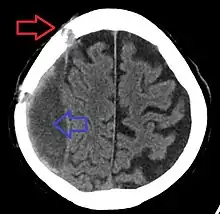

| Subdural hematoma as marked by the arrow with significant midline shift | |

On a CT scan, subdural hematomas are classically crescent-shaped, with a concave surface away from the skull. However, they can have a convex appearance, especially in the early stages of bleeding. This may cause difficulty in distinguishing between subdural and epidural hemorrhages. A more reliable indicator of subdural hemorrhage is its involvement of a larger portion of the cerebral hemisphere. Subdural blood can also be seen as a layering density along the tentorium cerebelli. This can be a chronic, stable process, since the feeding system is low-pressure. In such cases, subtle signs of bleeding—such as effacement of sulci or medial displacement of the junction between gray matter and white matter—may be apparent.